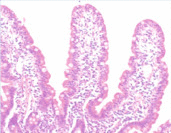

Small intestinal biopsy is an indispensable component of the diagnostic work-up of patients with malabsorption and/or chronic diarrhea secondary to mucosal damage. Though complete villous flattening usually indicates CD when coexisting crypt hyperplasia is present, there are entities that may cause villous flattening and crypt hyperplasia other than CD. The majority of disorders causing malabsorption, on the other hand, produce mild to moderate villus blunting and crypt hyperplasia without any specific diagnostic feature. Pathologists can also be faced with a patient with malabsorption or chronic diarrhea and a biopsy that appears normal or near-normal architecturally on microscopy. Table 3 highlights mucosal pathology of malabsorption.

Mucosal pathology in malabsorption

| Normal mucosa | IELosis | Villous shortening and crypt hyperplasia | Flat mucosa |

|---|---|---|---|

![]() |

Based on a substantial amount of clinical research including a sequence of dynamic studies, the morphological continuum of gluten sensitivity was first introduced by Marsh. Marsh classification is comprised of three consecutive states of mucosal damage (types 1–3), including infiltrative lesion (Marsh type 1) characterized by increased IELs in the villus epithelium in an otherwise normal mucosa with normal villous–crypt ratio, hyperplastic lesion (Marsh type 2) characterized by crypt hyperplasia with normal villi showing increased IELs, and destructive lesion (Marsh type 3) characterized by flat mucosa with crypt hyperplasia and increased IEL (Figure 6 ). In its classical form, CD results in shortened, widened villi or even totally flat mucosa with hyperplastic crypts (Figure 7(a) and 7(b)). These architectural changes are preceded by an increase in the number of IELs over the normal numbers (Figure 8(a) and 8(b)), corresponding to the cell-mediated immune nature of the disorder, and it is this group of cases that cause difficulty in the differential diagnosis.